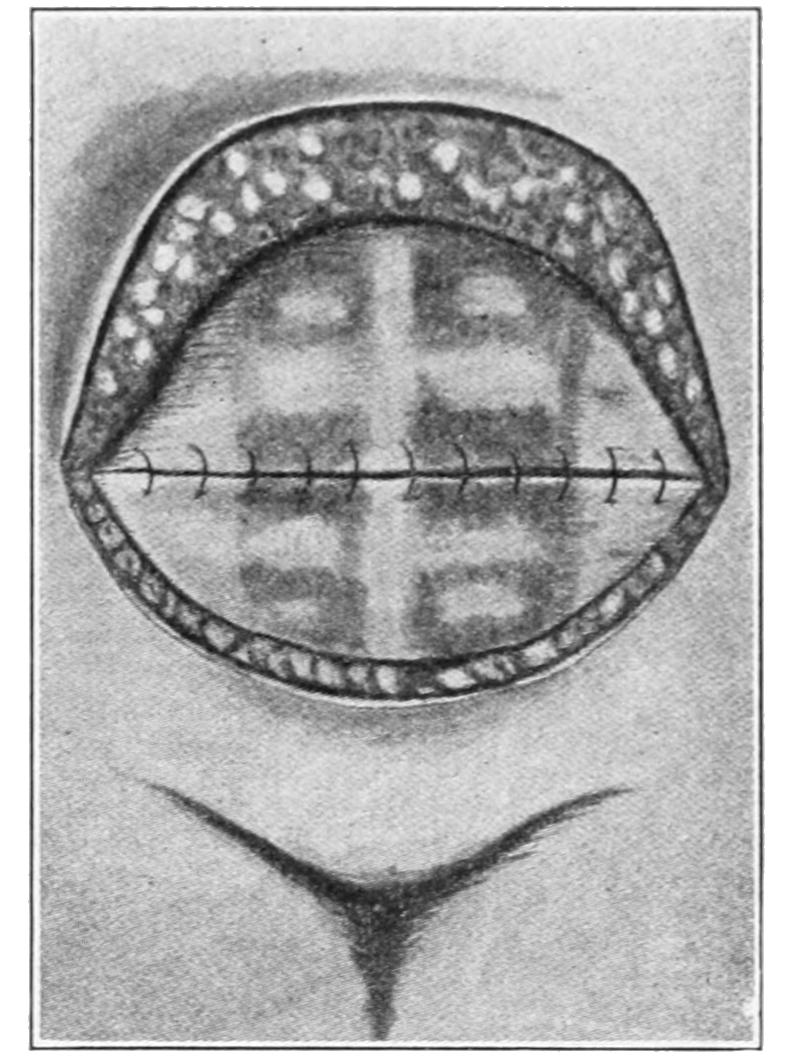

HERNIA 890